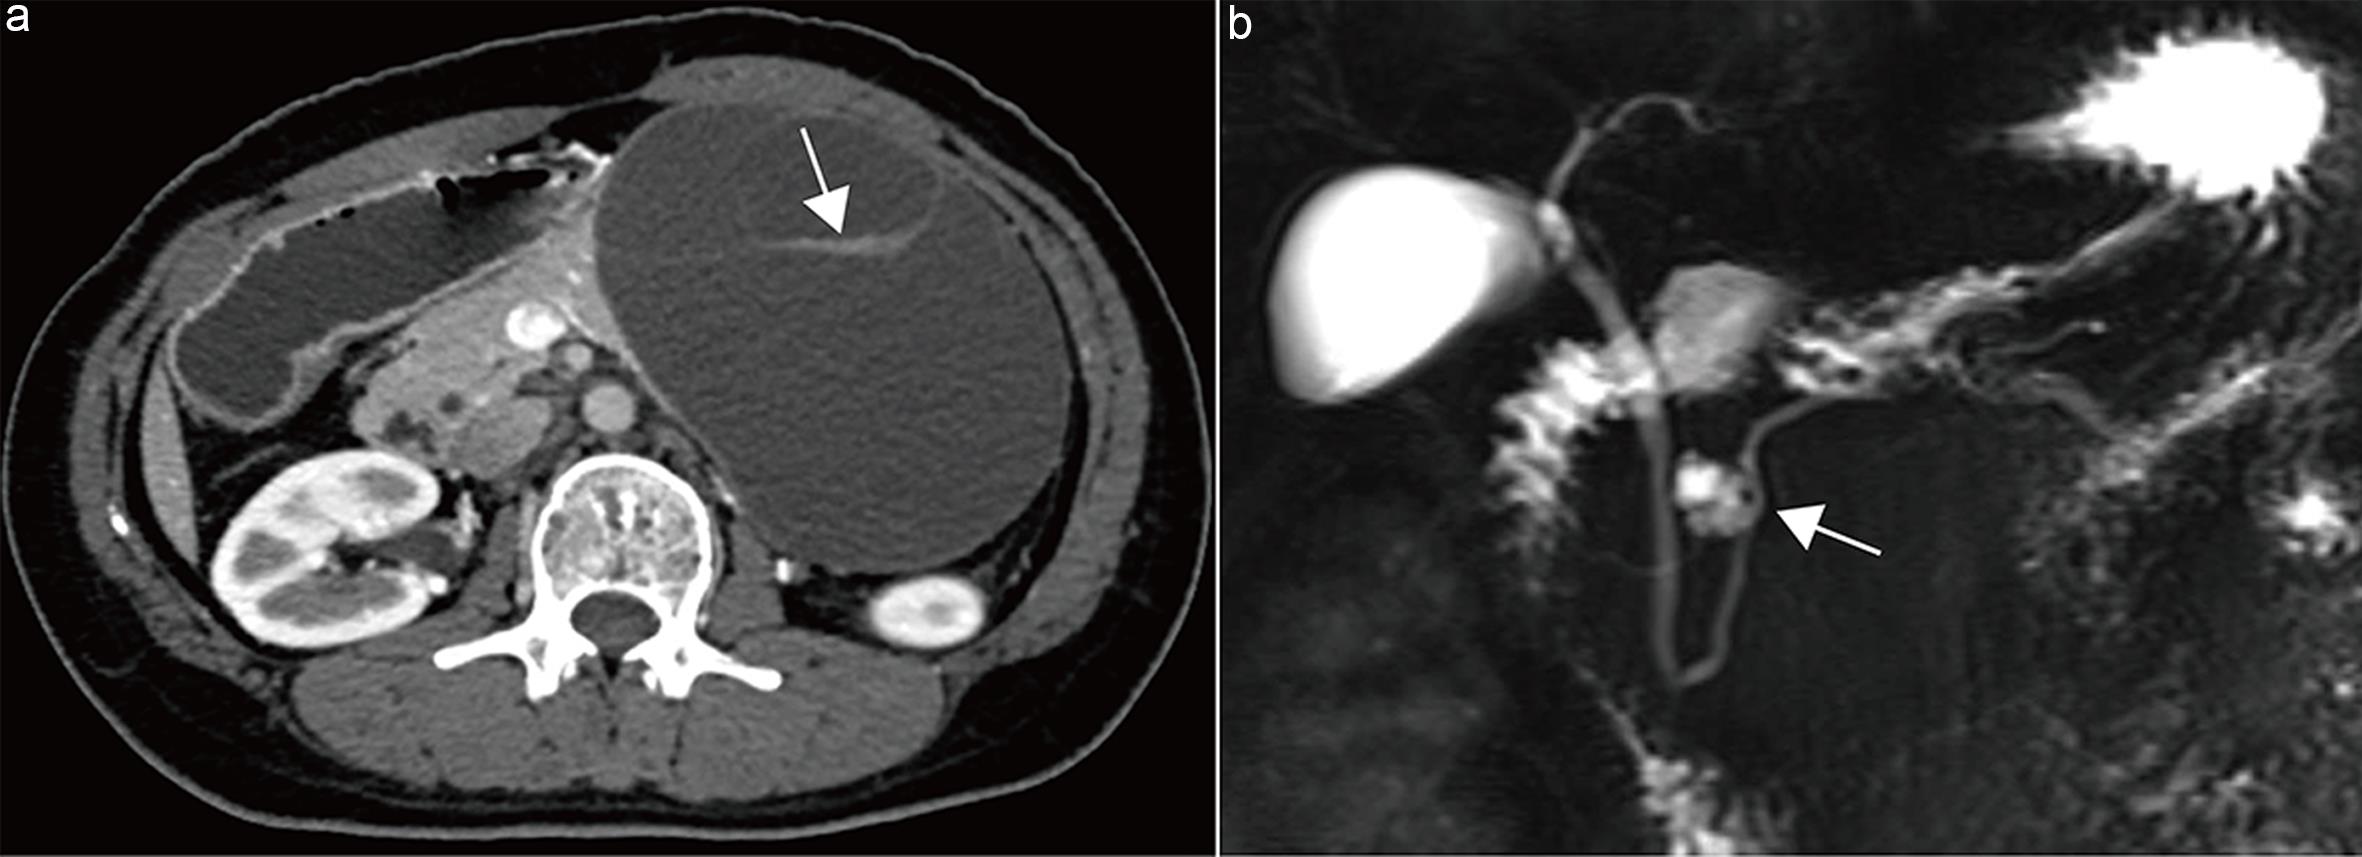

Recommendation 12: Morphological assessment of the main pancreatic duct obstruction point is necessary.

Morphologies of main pancreatic duct obstruction include stricture and abrupt cutoff; abrupt cutoff is particularly indicative of malignancy. Lim et al.47 developed a predictive model combining four factors—abrupt cutoff of the pancreatic head/neck duct, contour changes at the cutoff, associated acute pancreatitis, and elevated CA19-9—to differentiate malignant lesions in patients with duct dilation; the model achieved an AUC of 0.84 (95% CI 0.77–0.90).

A 2022 meta-analysis including nine studies found that duct stricture and the “duct-penetrating sign” are important imaging features distinguishing autoimmune pancreatitis from pancreatic ductal adenocarcinoma, while duct cutoff had the highest sensitivity (87%) for pancreatic ductal adenocarcinoma.48

In a meta-analysis of imaging predictors for branch duct IPMN malignancy, including six studies assessing duct cutoff, the AUC was 0.67 (95% CI 0.62–0.71), sensitivity 20%, and specificity 92%.23

The 2017 Revised International Fukuoka Consensus Guidelines list abrupt duct cutoff with upstream pancreatic atrophy as a worrisome feature for IPMN malignancy.21

Therefore, this guideline recommends that imaging reports explicitly state whether main pancreatic duct obstruction is present; if so, the location and morphology (stricture versus cutoff) should be clearly described (Fig. 6).

Main-duct intraductal papillary mucinous neoplasm (MD-IPMN).

Fig. 6  Main-duct intraductal papillary mucinous neoplasm (MD-IPMN).

Axial contrast-enhanced pancreatic parenchymal phase computed tomography (CT) image shows an abrupt cutoff of the main pancreatic duct in the pancreatic body (arrow).